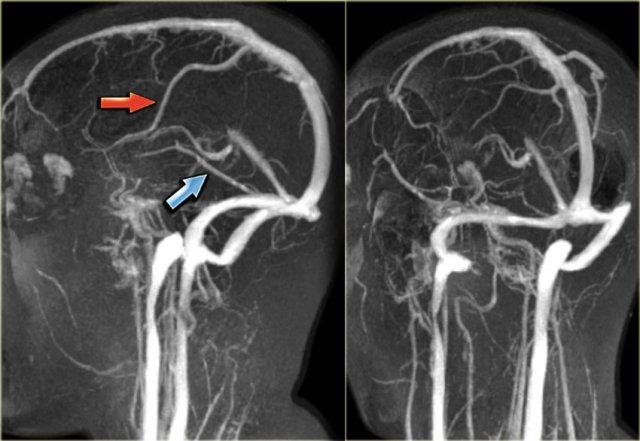

Bên trái là hình ảnh MIP theo mặt phẳng đứng dọc và chếch của một ca chụp tĩnh mạch MR có tiêm thuốc tương phản từ bình thường.

Lưu ý tĩnh mạch Trolard nổi bật (mũi tên đỏ) và tĩnh mạch Labbe (mũi tên xanh lam).

Các hình ảnh bên trái là của một bệnh nhân có xoang ngang trái kém phát triển.

Lưu ý sự chênh lệch kích thước của lỗ tĩnh mạch cảnh hai bên.

Bên trái là ảnh MIP mặt phẳng ngang (transverse MIP) của chuỗi xung tương phản pha (phase-contrast).

Để phân biệt xoang ngang kém phát triển với xoang ngang có huyết khối, cần xem xét các ảnh gốc (source images).

Trên ảnh gốc bên phải, có thể thấy không có tình trạng kém phát triển (mũi tên xanh).

Trong trường hợp này, đây là huyết khối xoang ngang trái.

Bên trái là một trường hợp khác minh họa rằng không thể hoàn toàn dựa vào kỹ thuật tương phản pha (phase contrast imaging).

Tín hiệu trong tĩnh mạch phụ thuộc vào vận tốc dòng máu chảy và thông số mã hóa vận tốc (velocity encoding) do kỹ thuật viên cài đặt.

Ở ngoài cùng bên trái là hình ảnh bệnh nhân không thấy xoang ngang trái.

Điều này có thể do kém phát triển, huyết khối tĩnh mạch hoặc dòng chảy chậm.

Trên chuỗi xung T1W sau tiêm thuốc tương phản từ, có thể thấy rõ ràng xoang ngấm thuốc và còn thông (patent).